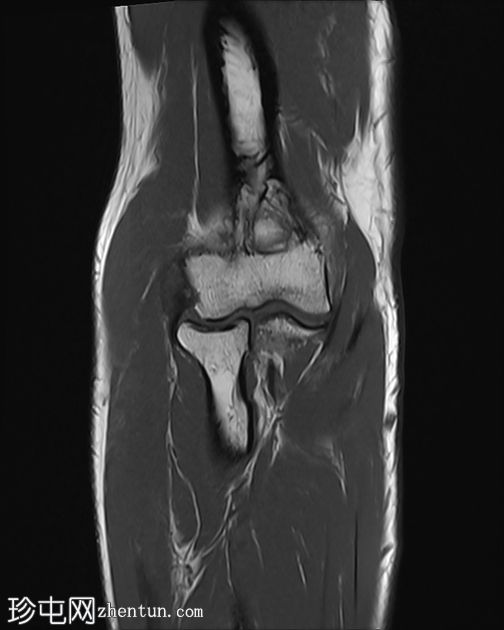

冠状位

T1加权像

肘关节伸肌总腱增厚,腱内可见高信号及部分撕裂。伴周围软组织水肿。

本病例展现了网球肘的典型

影像

学特征。